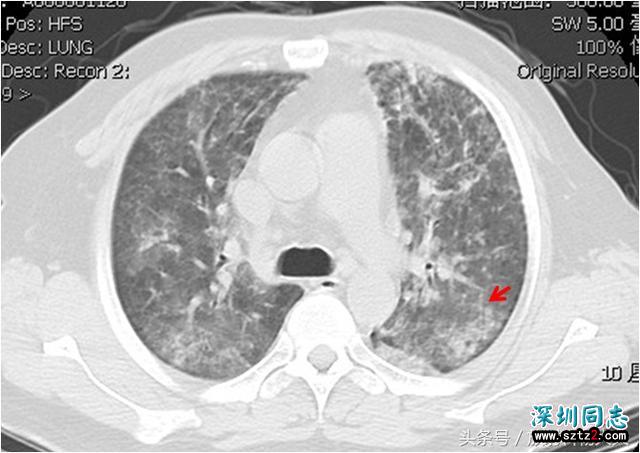

肺孢子菌在正常人群中也有,可以通过空气传播,但健康人群有强大的免疫系统保护,并不会发病;但艾滋病病人免疫系统缺陷,很容易感染,感染后可导致病人出现干咳、呼吸急促及发热等,高分辨CT是最佳检查方法,影像学表现也比较多样,可呈毛玻璃影、碎石路征、实变及结节等等。

影像学上有所谓的同像不同病,病史对于影像诊断非常重要,一张PCP的片子在眼前, 放射科医生一定要了解病史,比如本文背景中介绍的,是否是艾滋患者,假如没法直接问,可以委婉的问问性取向如何之类,性取向本身不是问题,但假如性活动的时候不保护自己,那就是自己的错了。